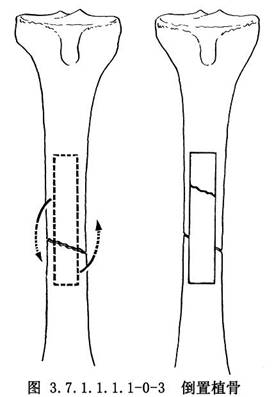

皮質骨剝離術系Judet所倡導,其方法是切口直達骨質,在骨膜下鑿去薄層骨片,但必須保持骨片與周圍軟組織的血運聯繫。皮質骨剝離範圍佔骨周徑1/2~2/3(圖3.7.1.1.1.1-0-1)。兩骨折端均須做皮質骨剝離,並使骨與其外覆蓋的軟組織之間形成袋狀,以便同時做骨折端周圍植骨(phemister bone graft)(圖3.7.1.1.1.1-0-2)。但在對位對線較好,纖維瘢痕可維持骨折端穩定時,通常是將細條形松質骨置於骨折端瘢痕周圍。對切除整新骨端而形成斷端間隙或缺損者,須用松質骨嵌入移植,以免喪失肢體長度。滑行植骨(sliding bone graft)亦稱倒置植骨,方法是在骨折端兩側切取不等長的長方形骨條,其寬度不超過骨幹周徑的1/3。將條狀骨倒置,使較長的骨塊騎跨骨折端兩側(圖3.7.1.1.1.1-0-3)。髓腔內植骨(medullary bone graft)(圖3.7.1.1.1.1-0-4)是用一側帶皮質的柱狀骨塊插入骨折端兩側髓腔內,有加強固定穩定性和促進成骨的雙重效果。長骨幹不愈合骨折用單純植骨術治療的適應證很少,一般都需同時使用堅固的內固定或外固定,爲骨癒合提供生物學和力學兩方麪條件。